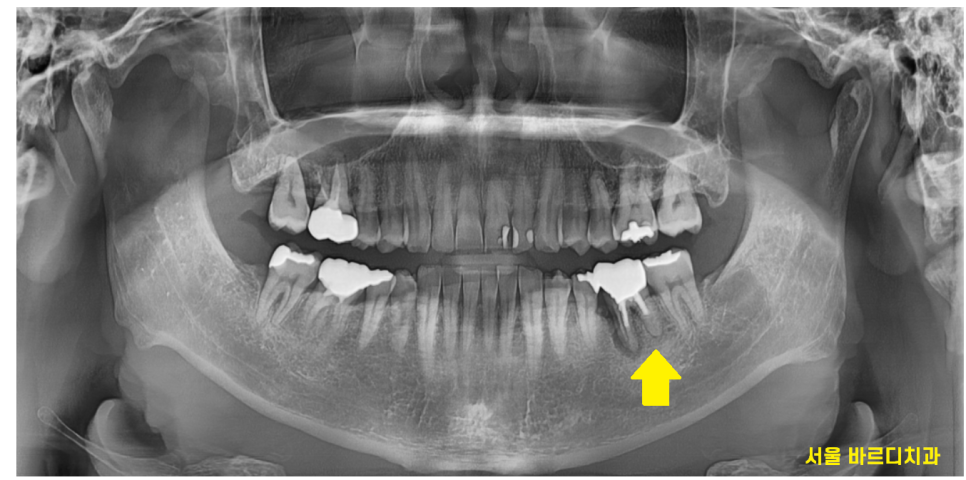

3년만에 치과를 방문해주신 환자분 사진입니다.

그동안은 바쁘기도 하고

불편한게 없어서 안오셨다고 하네요.

최근에 아몬드를 씹고 나서

치아가 계속 아프다고 하셨는데요.

큰 사진에서도 문제가 많아보였습니다.